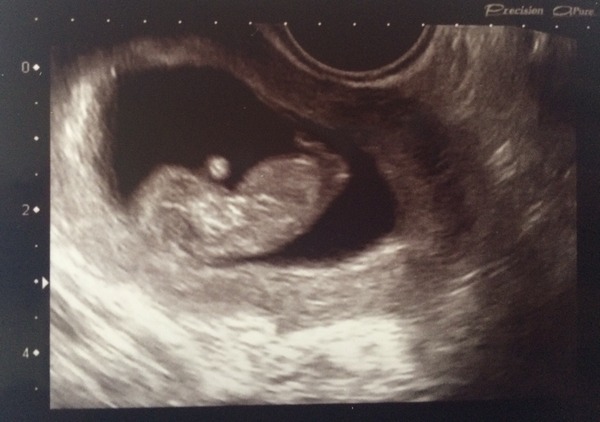

Here's my little alien baby! Grin I think it's waving?!